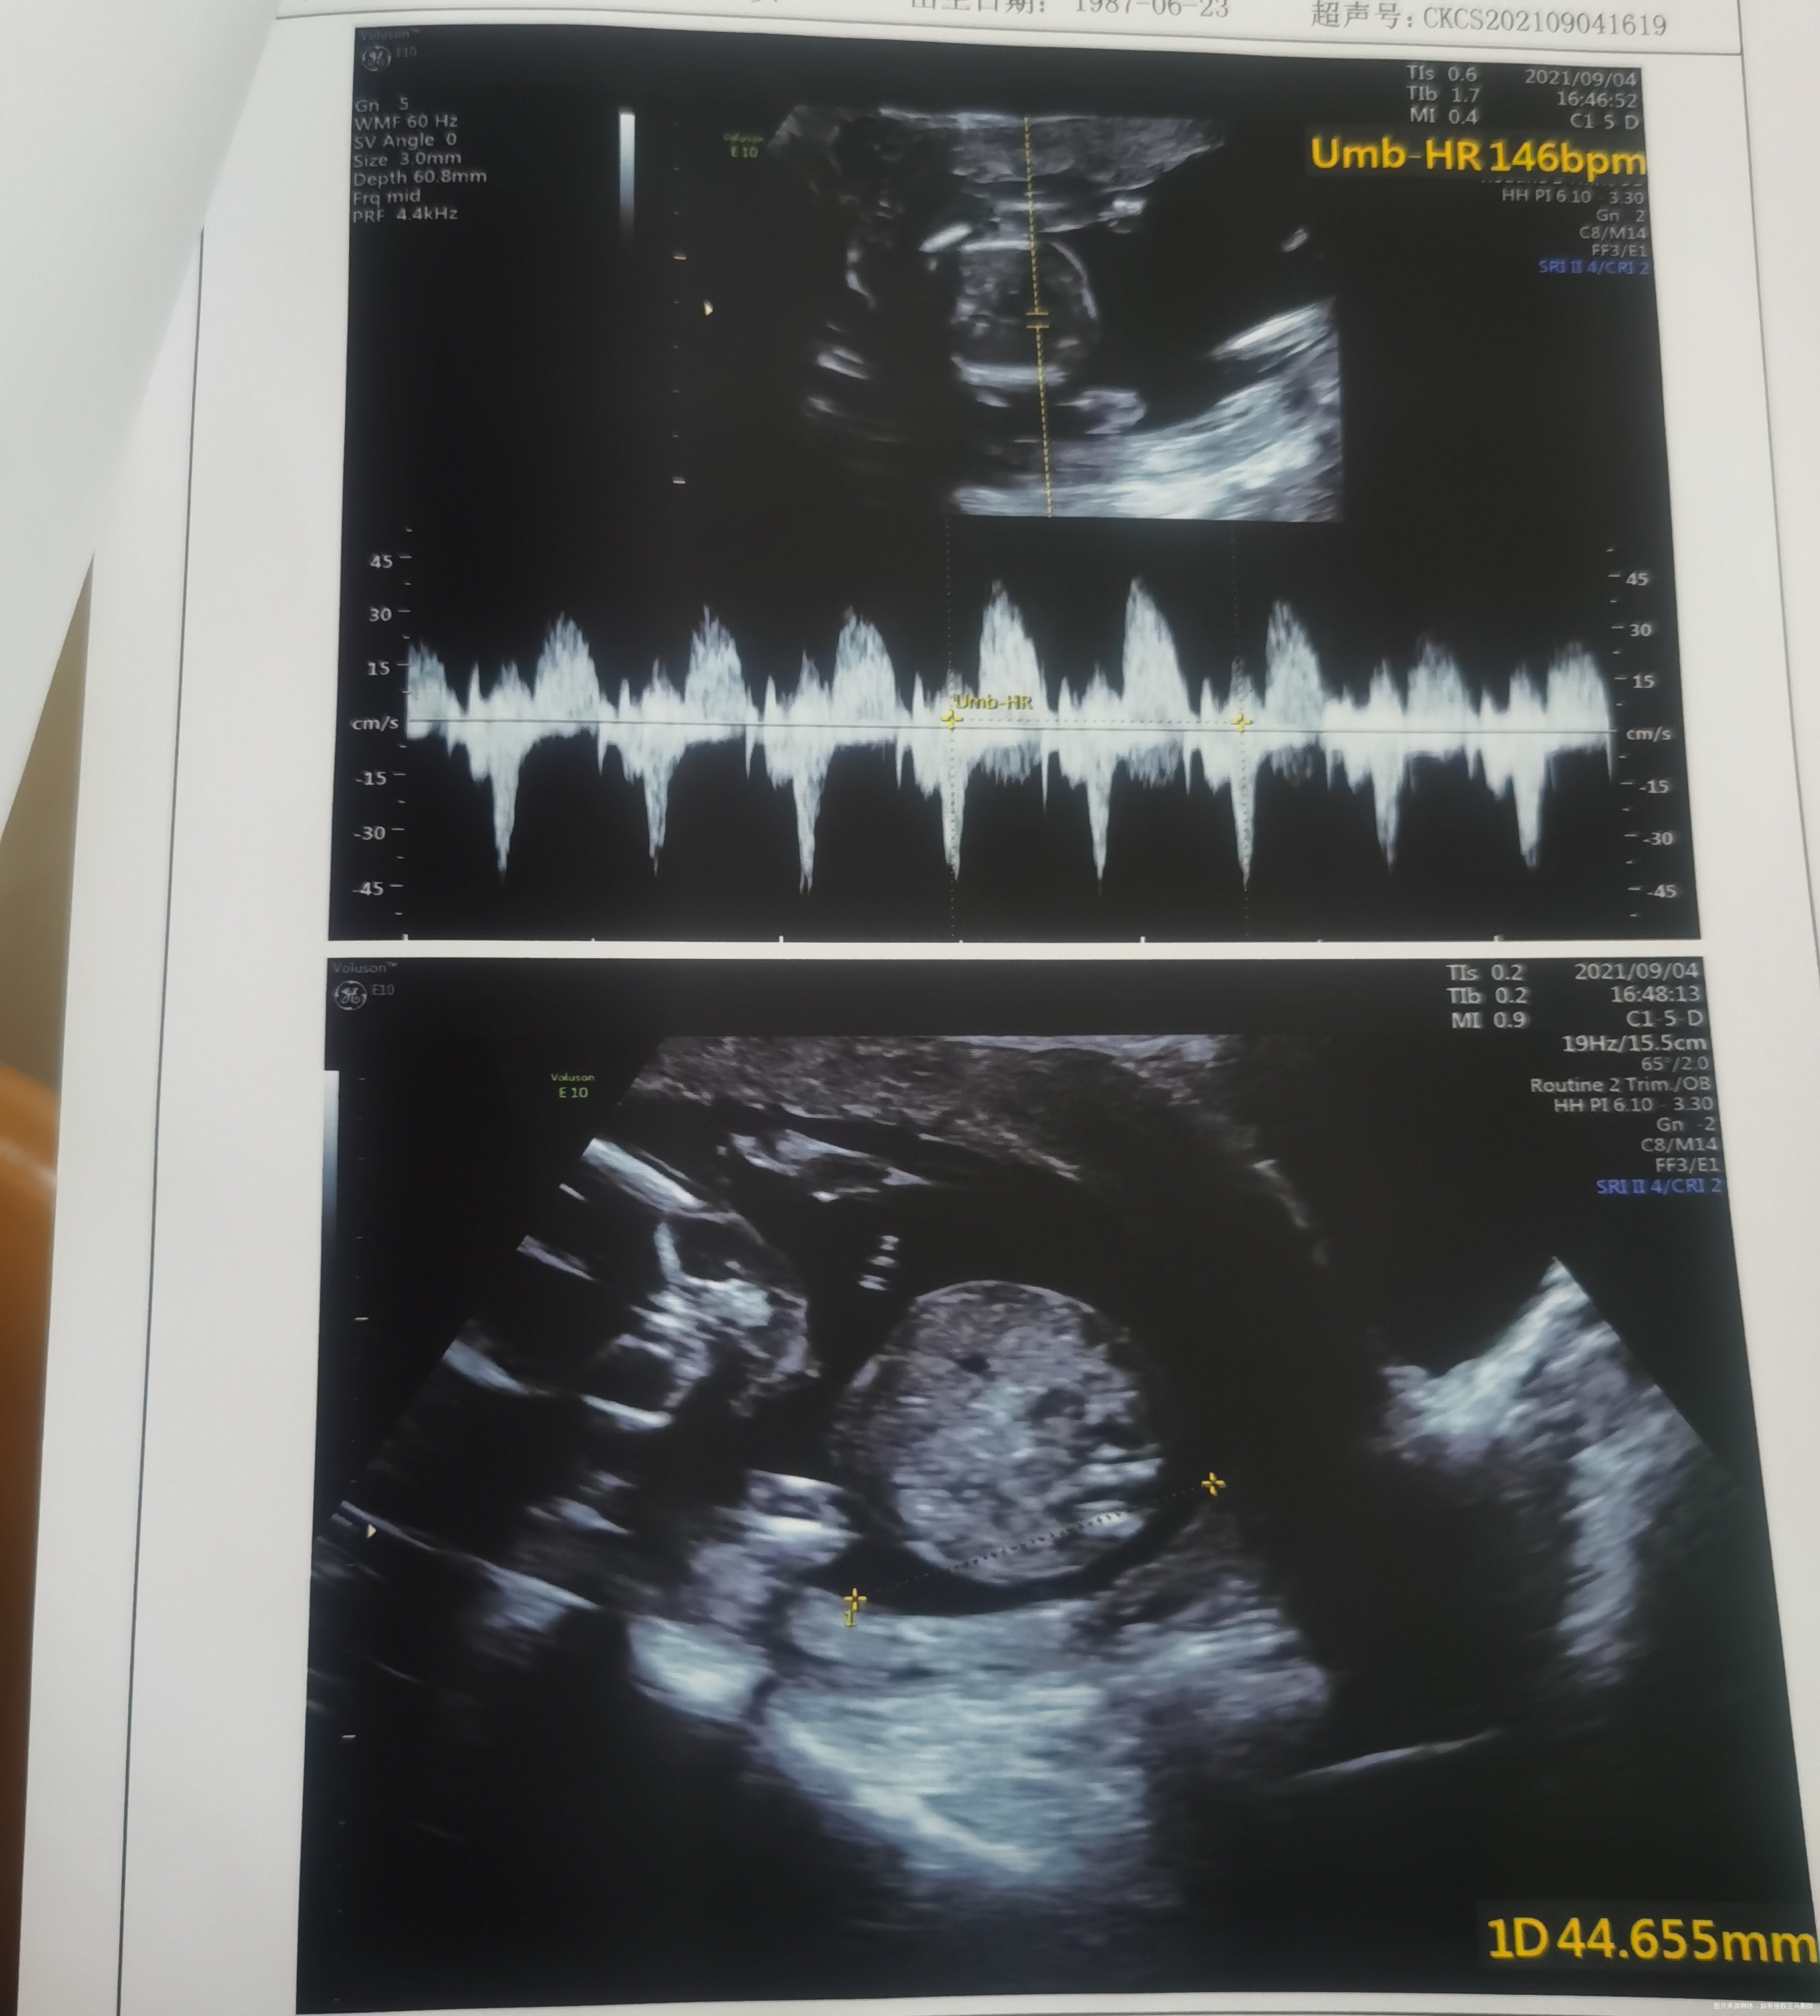

请医生帮我看一下:1、我有没有羊水过多?2、我的胎盘是不是离宫颈口较远(之前是描述距离近),不用担心胎盘低置问题了?3、我的子宫是左旋子宫还是右旋呢,我应该靠左侧睡还是右侧睡更好?仰睡真的会影响宝宝 可能导致缺氧么?4、宝宝的股骨是不是偏小?需要加强补钙么?目前我每天吃一颗醋酸钙。5、我之前的B超都是头位 现在变成臀位了,请问后面是不是还会变化?

羊水量正常,胎盘位置可以的,不是低置,胎盘在后壁不要仰卧睡,一般左侧睡。股骨现在还太小,正常发育就可以的,可以补钙的,头位臀位现在可以变化的。

目前怀孕刚刚4个月 胎位不固定的 一般孕7个月后胎位才会固定 目前胎盘位置正常 羊水也在正常范围之内 放松心情 定时产检

羊水一个平面大于80mm叫羊水过多,你刚刚好不多,胎盘位置不低,子宫右旋左旋要到晚孕,产检是看,一般左侧睡为主,晚孕期最好不要仰卧,增大子宫压迫,血液回流减少回出现心慌气短,出冷汗现象,股骨短不短要结合末次月经推算孕周综合考虑,补钙量可以,目前臀围不管它,30周后注意胎位。